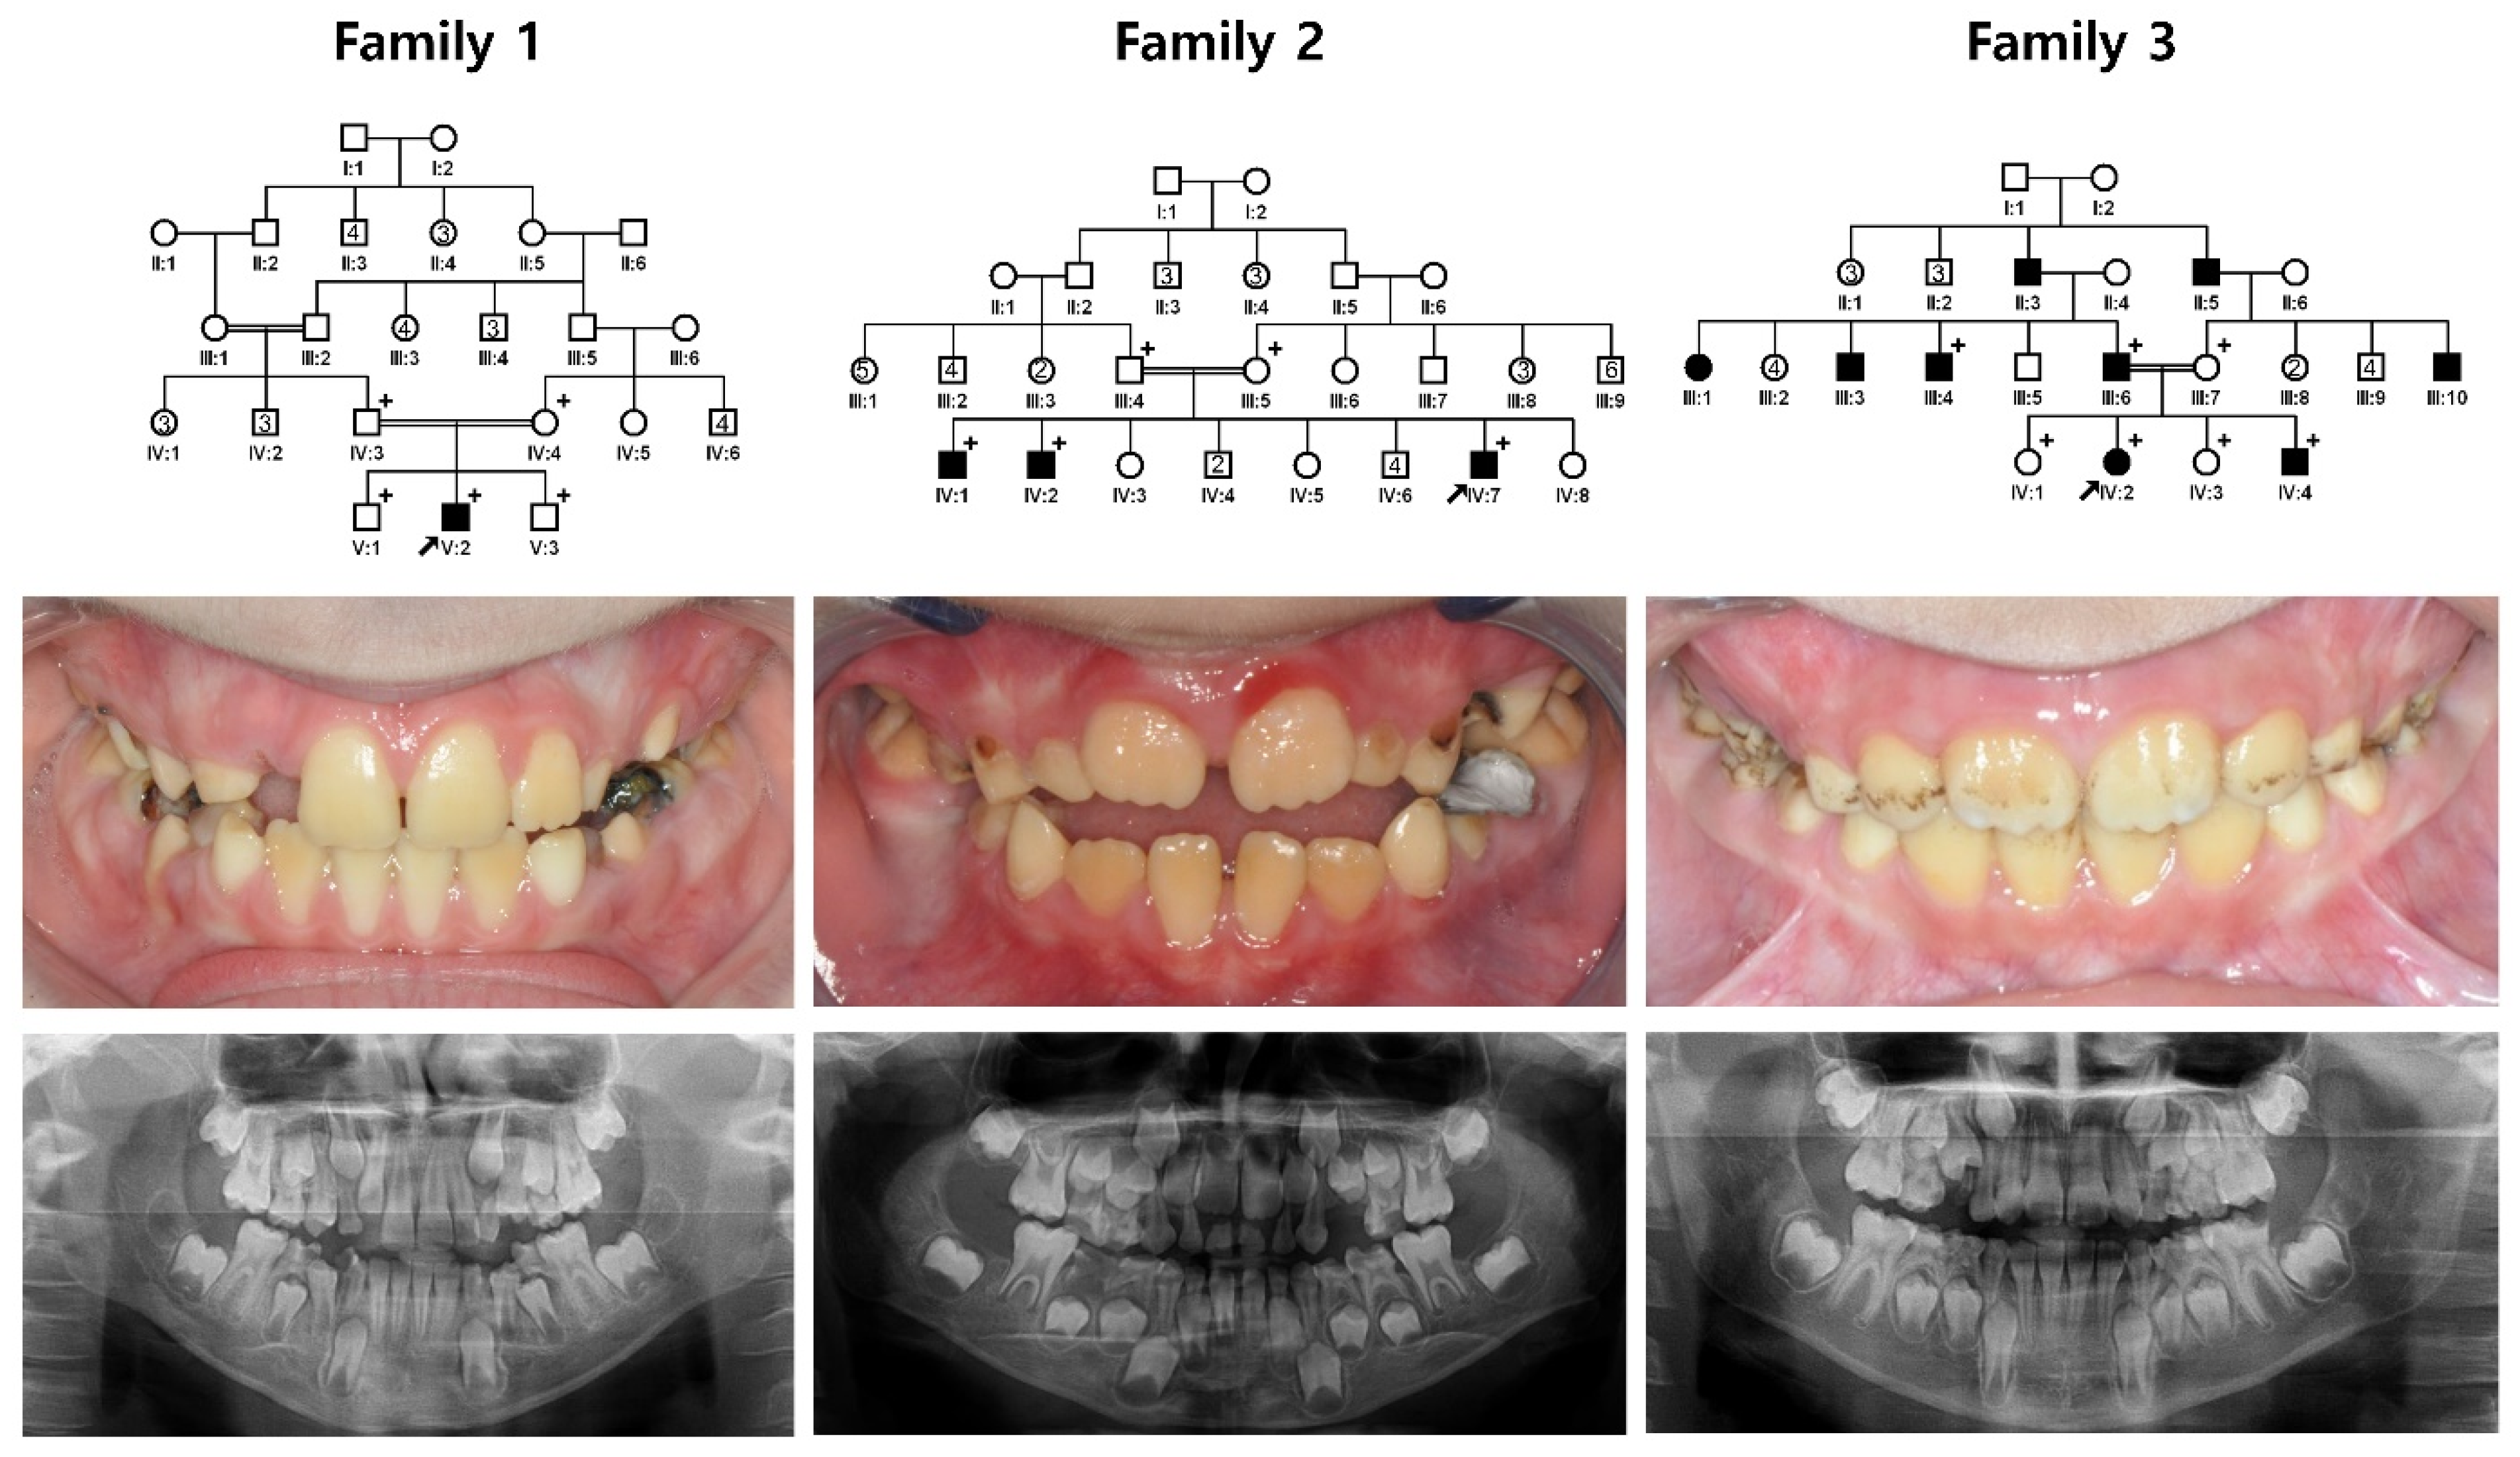

3.1. Family 1~3